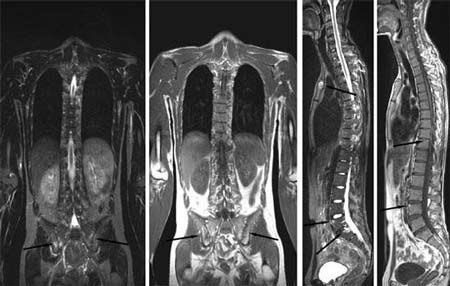

刘先生来自许昌市魏都区,(郑州痛风风湿病医院提供),他于7年前患上强直性脊柱炎,初时全身疲乏无力,间断低热,由于症状较轻,并未引起重视。后病情加重,导致颈椎、骶髂关节疼痛,伴有晨僵现象,经当地...[详细]

来自开封市鼓楼区的患者李先生来到我院(郑州痛风风湿病医院)后,自述于六年前患上强直性脊柱炎,初期疲劳乏力,厌食消瘦,但并未提高警惕,及时前往医院治疗,导致病情加重,脊柱、骶髂关节持续性疼痛。后...[详细]